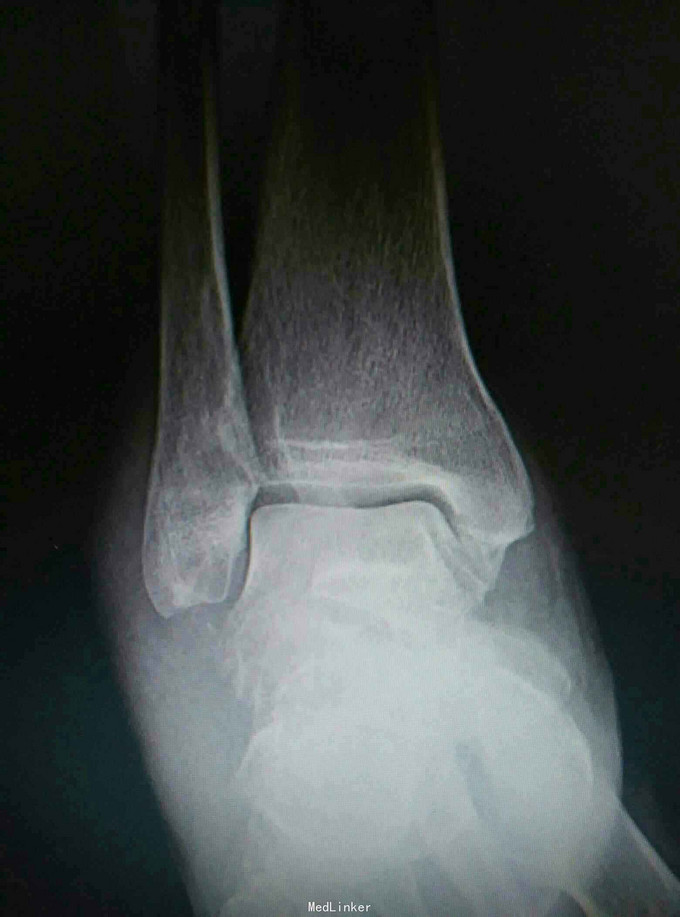

患者,男,45岁,车祸伤致右踝部肿痛,活动受限2小时入院

入院查体见局部肿胀,予完善影像学检查,

诊断是右距骨粉碎性骨折。给予行内踝截骨显露骨折端进行复位,采用Herbert钉进行固定。

术后复查X线片提示骨折端完全复位,内固定固定在位良好。 讨论:距骨骨折的主要并发症是坏死,骨不愈合等,但近年来随着对其认识的不断明确,治疗比较规范,积极的进行切开复位,并行坚强固定,近年的研究报告提示距骨的坏死率是不断在下降的,当然前提是进行有效复位并坚强固定。